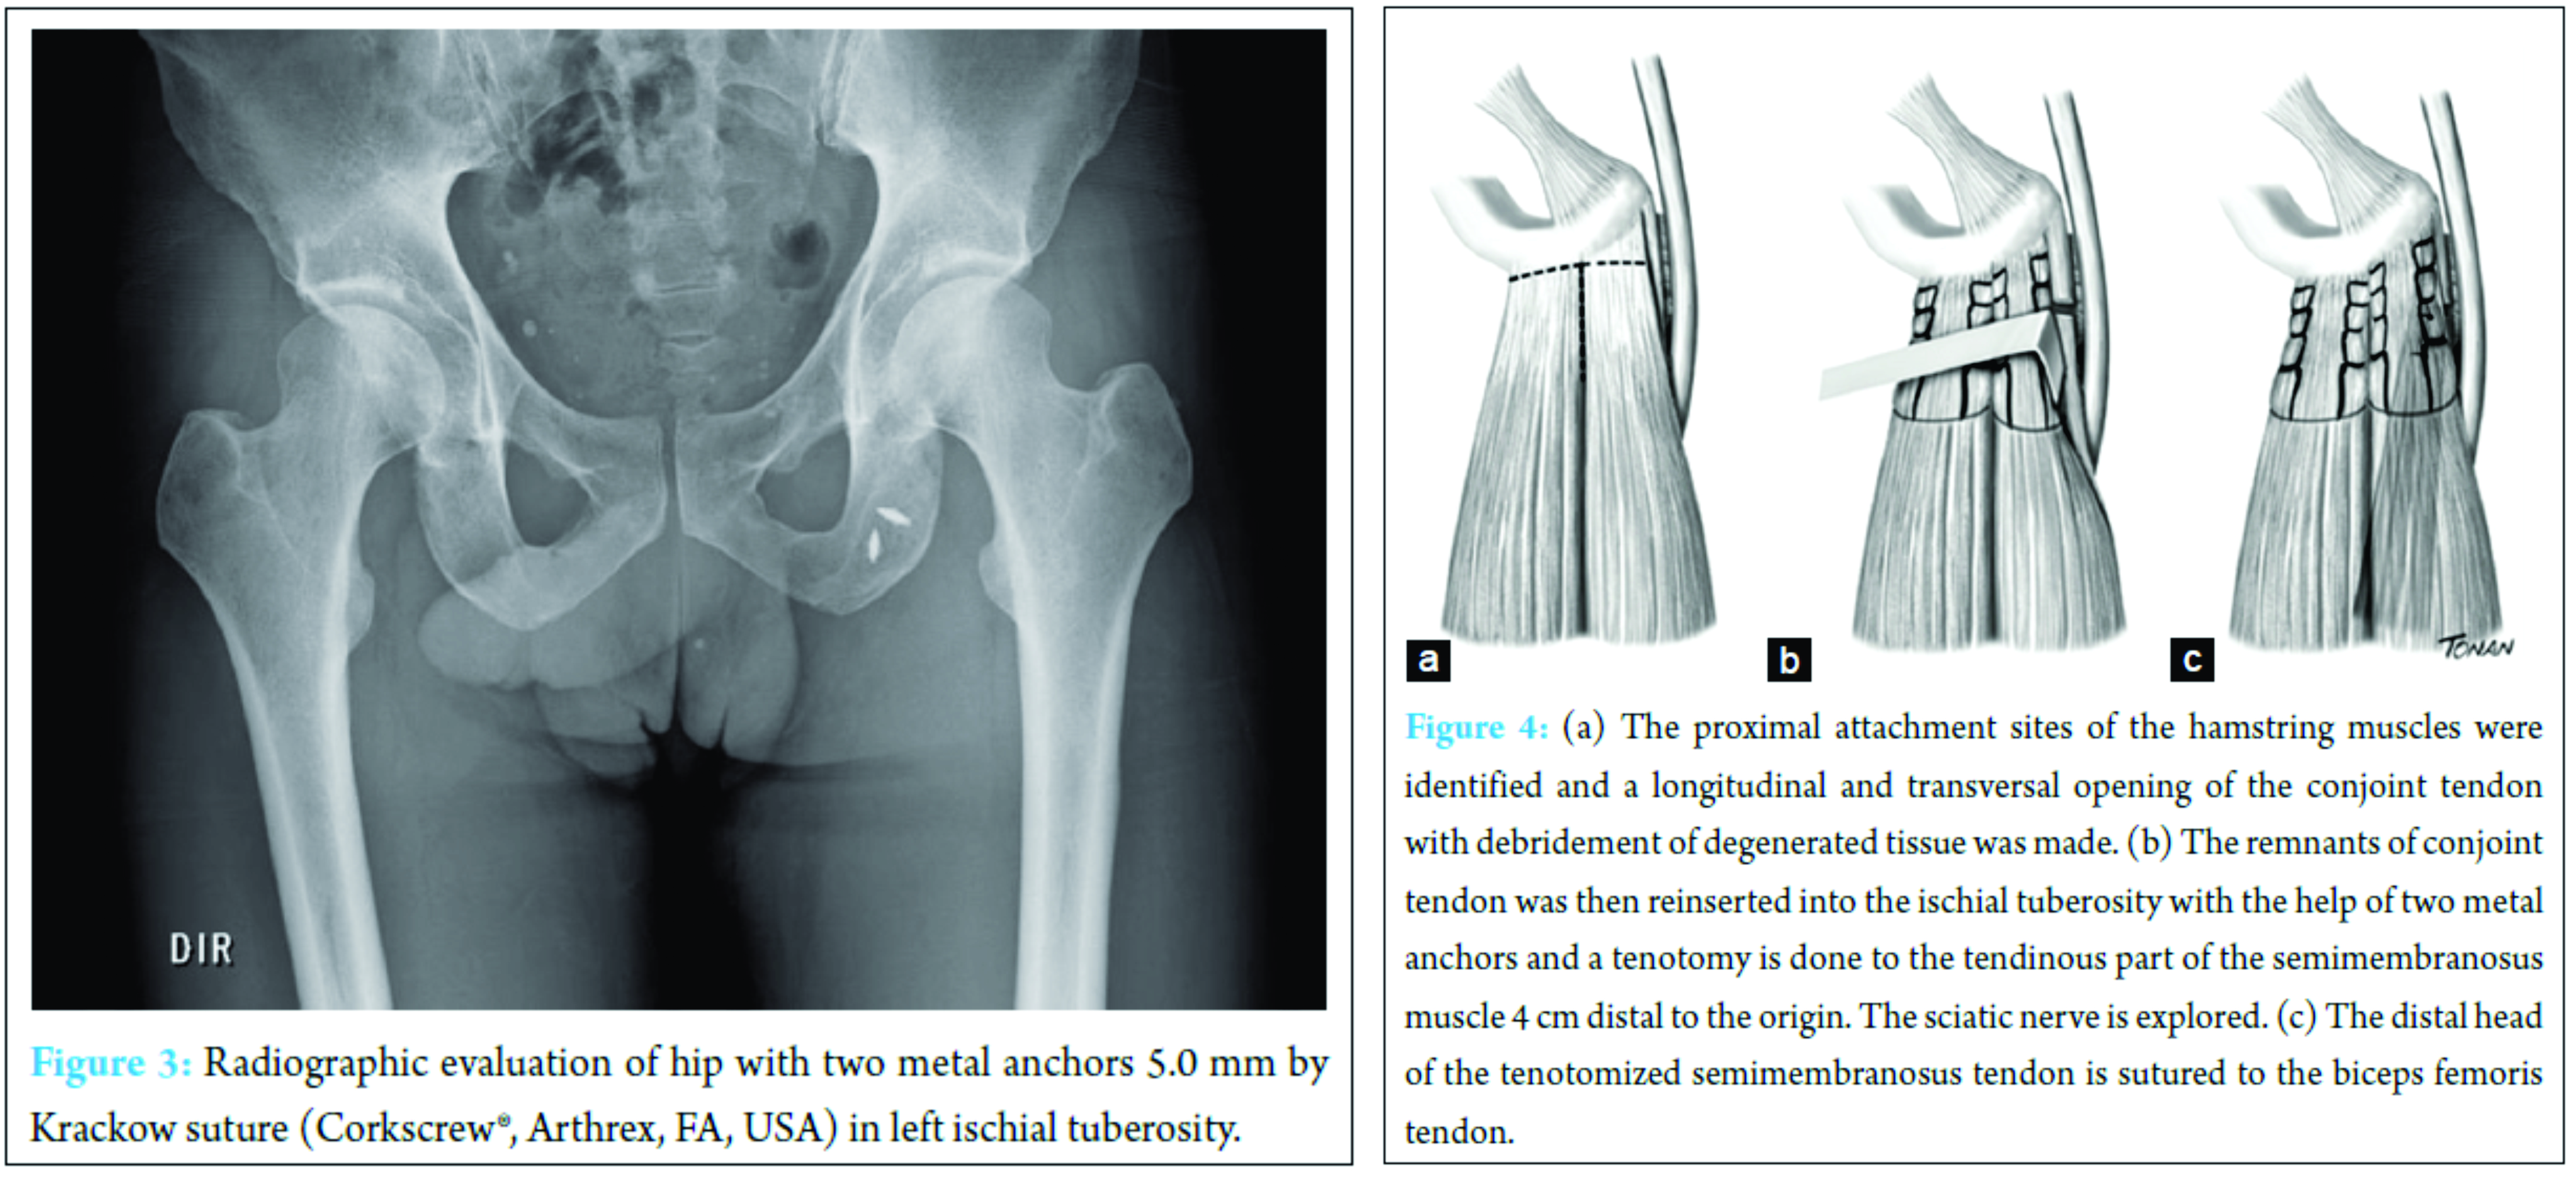

Surgery was performed under spinal anesthesia with the patient in the prone position and the knee slightly flexed to relax the hamstring muscles and the sciatic nerve. A transversal posterior incision in the gluteal fold centered in the ischial tuberosity of 6 cm was made. The lower edge of the gluteus maximus muscle was freed and the posterior cutaneous femoral nerve was identified and spared. The ischial tuberosity was easily exposed by retraction of the inferior border of the gluteus maximus muscle. The proximal attachment sites of the hamstring muscles were identified (Fig. 2) and a longitudinal and transversal opening of the conjoint tendon with debridement of degenerated tissue was made. The remnant tendon was then reinserted into the ischial tuberosity with two metal anchors 5.0-mm by Krackow suture (Corkscrew®, Arthrex, FA, USA). After this, a transversetenotomy was done to the thickened semimembranosus tendon 4 cm distal to the origin. The tenotomized semimembranosus tendon was then sutured securely to the biceps femoris tendon to prevent excessive retraction. After tenotomy, the sciatic nerve was explored and the adhesions were freed (Fig. 3).

The surgical procedure is an alternative for patients with chronic, debilitating and refractory symptoms [7]. The semimembranosus tenotomy is the classical choice for being one of the most affected in PHT, transfering stress from the semimembranosus tendon to the biceps femoris and to the semitendinosus muscles. This stress-shielding may assist the semimembranosus tendon to recover [8,12]. The difference of the technique presented in this case relates to the fact of incorporating debridement of degenerated tissue with reinsertion of remnant tendon into the ischial tuberosity, which until the present has not been described for the treatment of chronic conditions; this reinsertion takes into account the anatomy of the proximal hamstring described by Philippon et al. [21]. The elimination of fibrous scar tissue combined with intermuscular suturing allows integral healing of muscle to muscle. It is believed that this decreases the chances of re-injury by eliminating the remodeling tissue that attempts to heal the musculotendinous injury. In addition, it allows the muscle to heal to the adjacent muscle in a tension-free manner, and thus, a stronger healing process will occur [2, 11, 18].